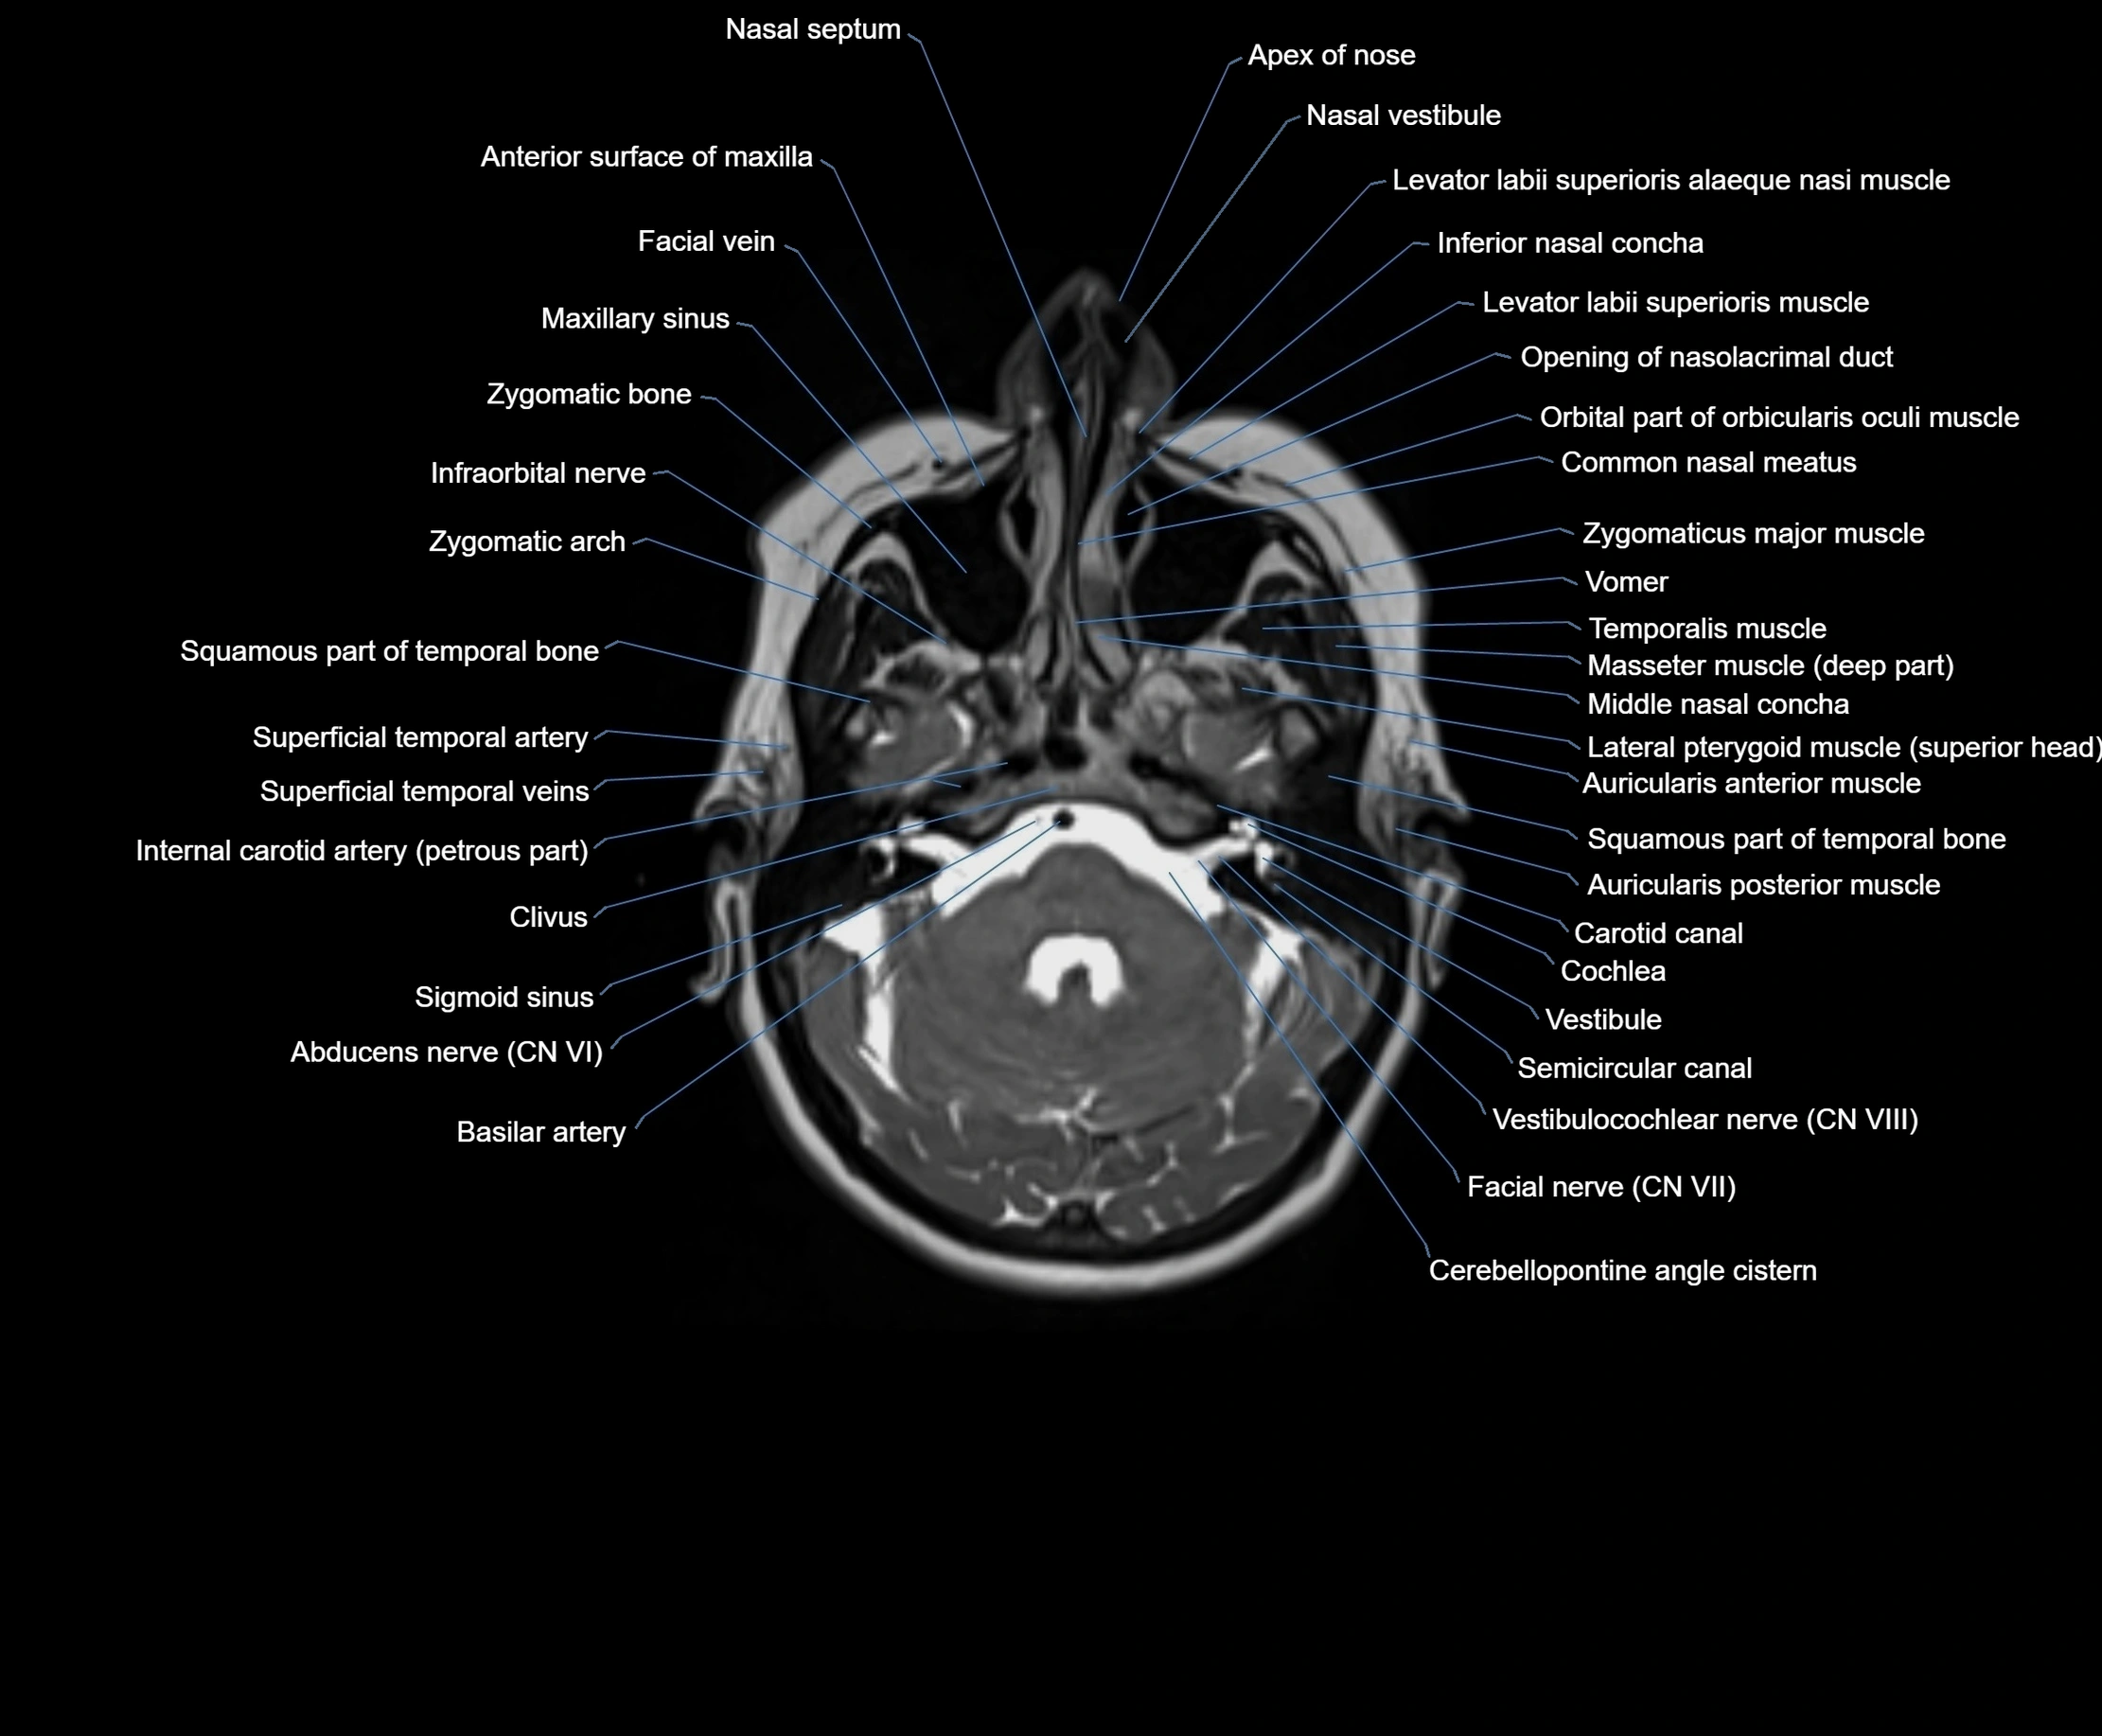

MRI images